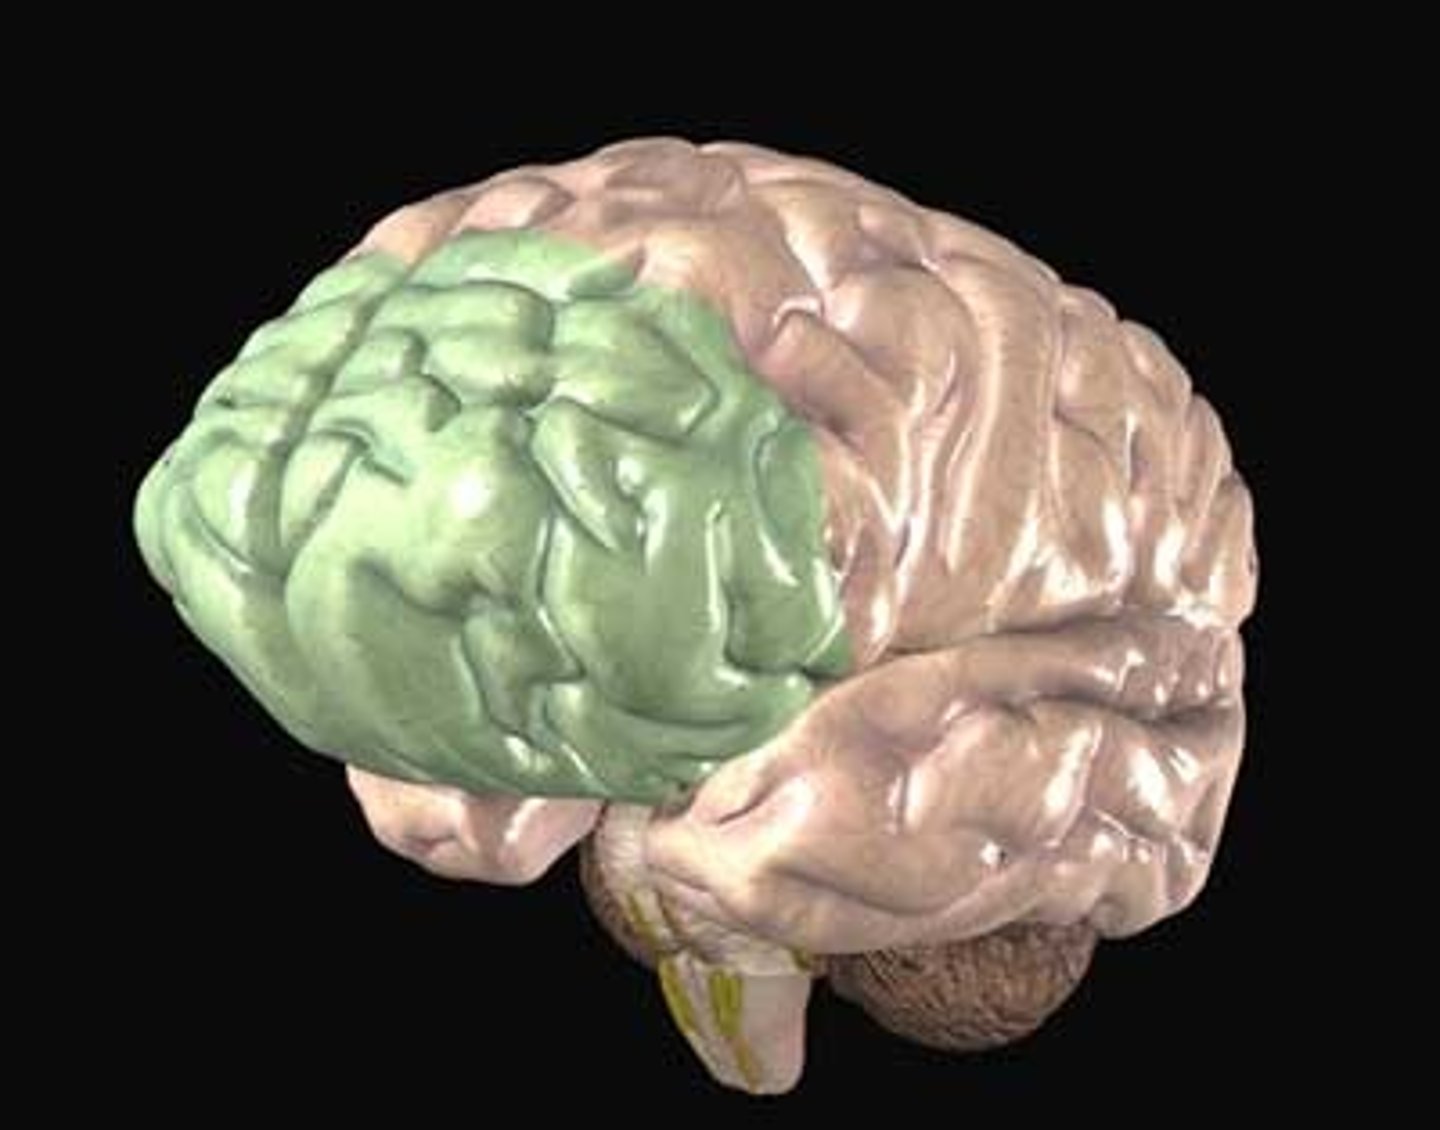

frontal lobes

portion of the cerebral cortex lying just behind the forehead; involved in speaking and muscle movements and in making plans and judgments.

parietal lobes

portion of the cerebral cortex lying at the top of the head and toward the rear; receives sensory input for touch and body position.

pre-frontal cortex

is the cerebral cortex which covers the front part of the frontal lobe; primary spot for decision making

Broca's Area

found in the left frontal lobe that is in charge of speech production

Right brain hemisphere specialization

Side of the brain responsible for colors, daydreaming, 3D, rhythm, imagination, geometry, distance, sense of direction, faces, emotional expressions

Left brain hemisphere specialization

Side of the brain responsible for words, letters, language, verbal memory, numbers lists, logic, analysis